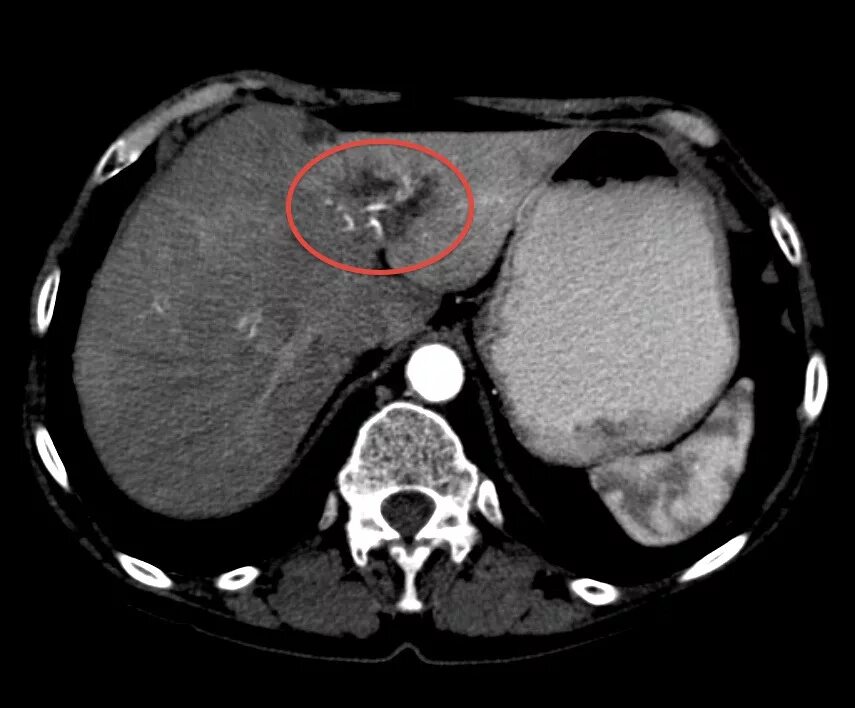

Гиподенсивное образование что это значит